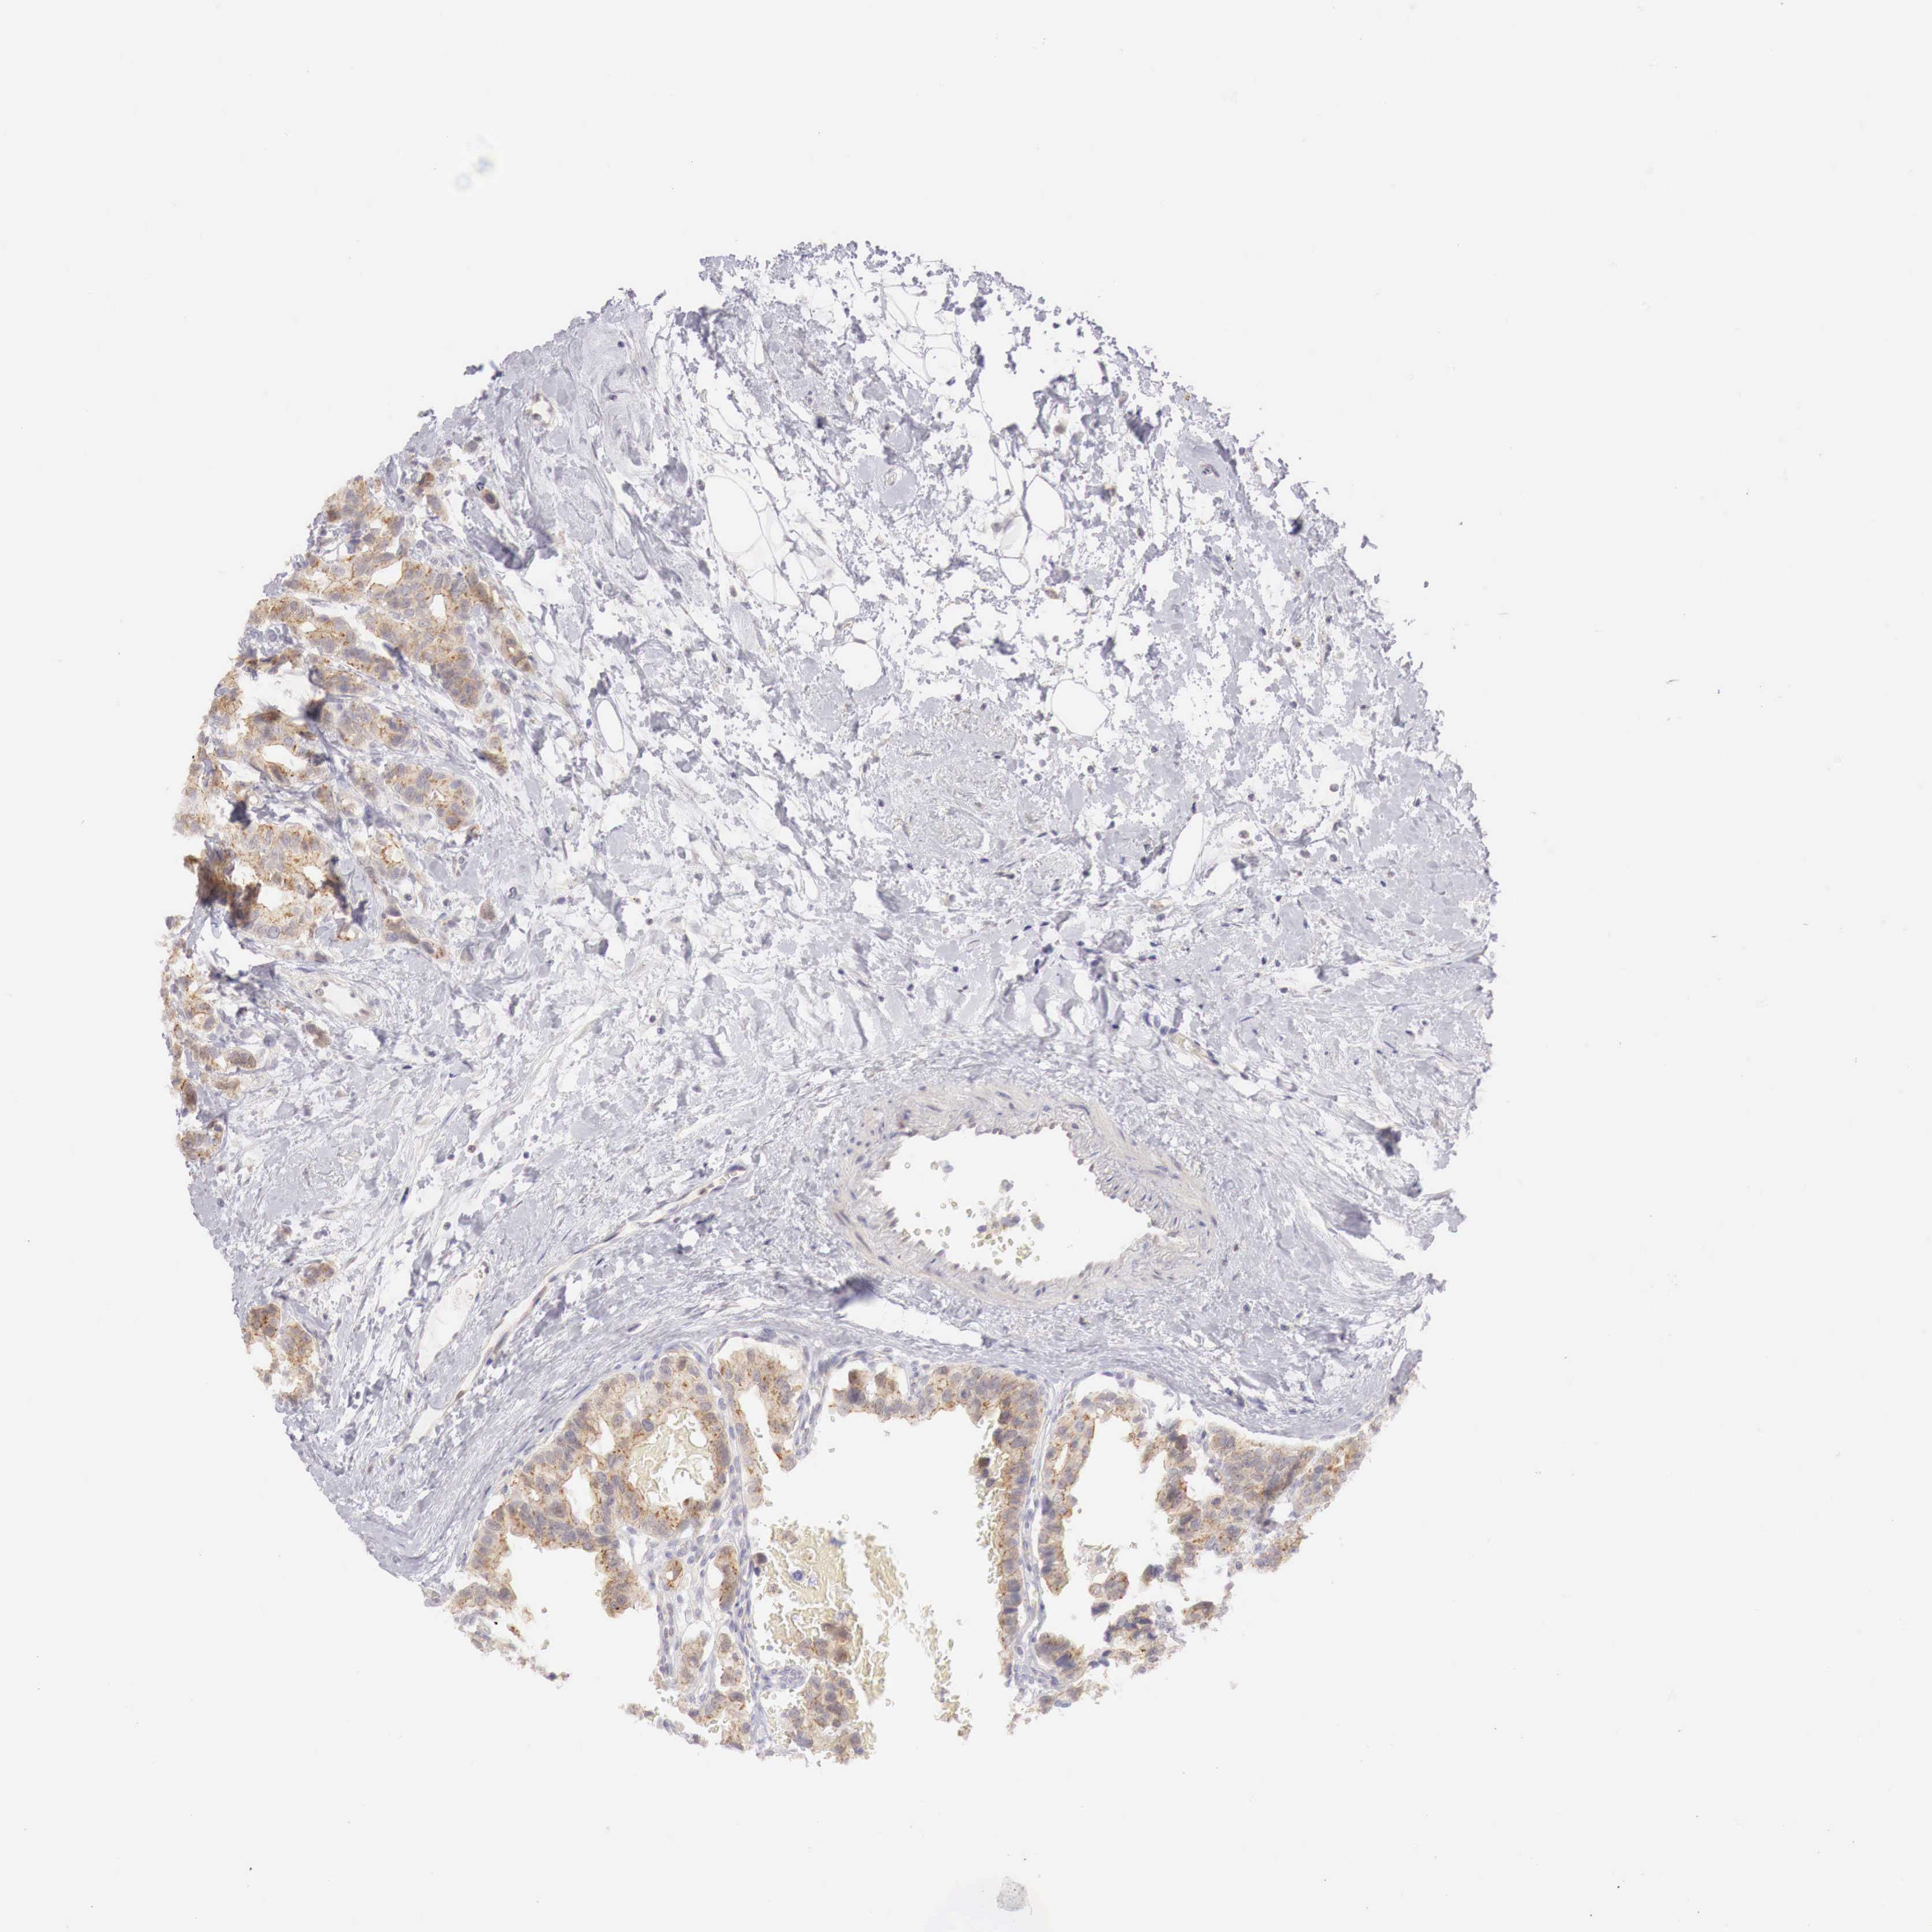

CANCER BREAST CANCER Show tissue menu

Breast cancer

Human cancer